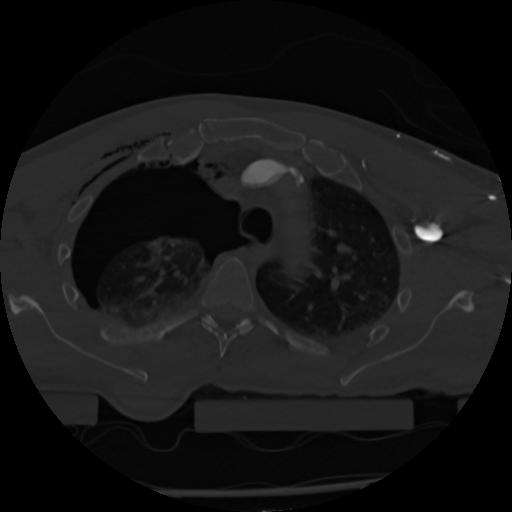

22 ANGIO,CE,Vol,0.5,ANGIO,,